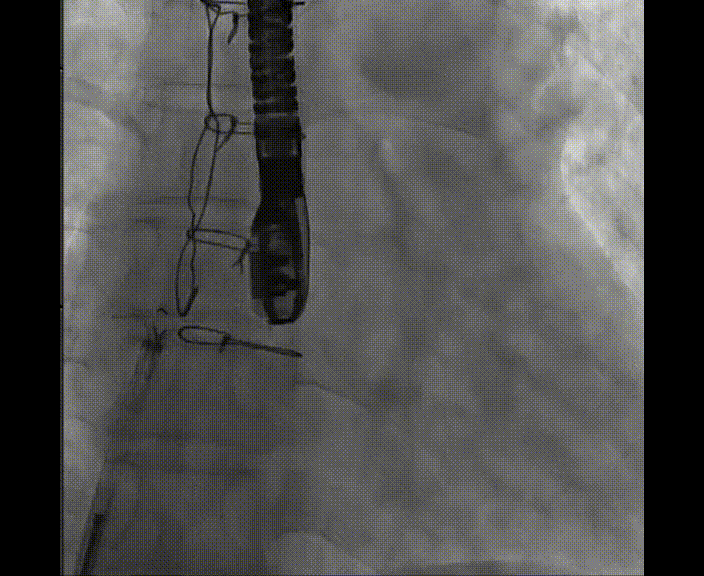

術(shù)中首先在局麻下穿刺股動(dòng)脈、股靜脈,完成心導(dǎo)管檢查評(píng)估后轉(zhuǎn)為全麻,在食道超聲引導(dǎo)下穿刺房間隔,穿刺成功后將加硬導(dǎo)絲送入左上肺靜脈建立軌道,根據(jù)患者病情行球囊預(yù)擴(kuò)張后植入6mm孔徑房間隔造孔支架,經(jīng)透視及食道超聲評(píng)估支架左右盤(pán)展開(kāi)良好,夾持于房間隔兩側(cè),固定穩(wěn)定、位置良好,食道彩超顯示房水平右向左為主分流,分流孔直徑符合預(yù)期大小,心導(dǎo)管檢查評(píng)估達(dá)到預(yù)期效果,釋放造孔支架。術(shù)后12h患者下床活動(dòng),恢復(fù)順利,擬于近日完善術(shù)后評(píng)估后出院。